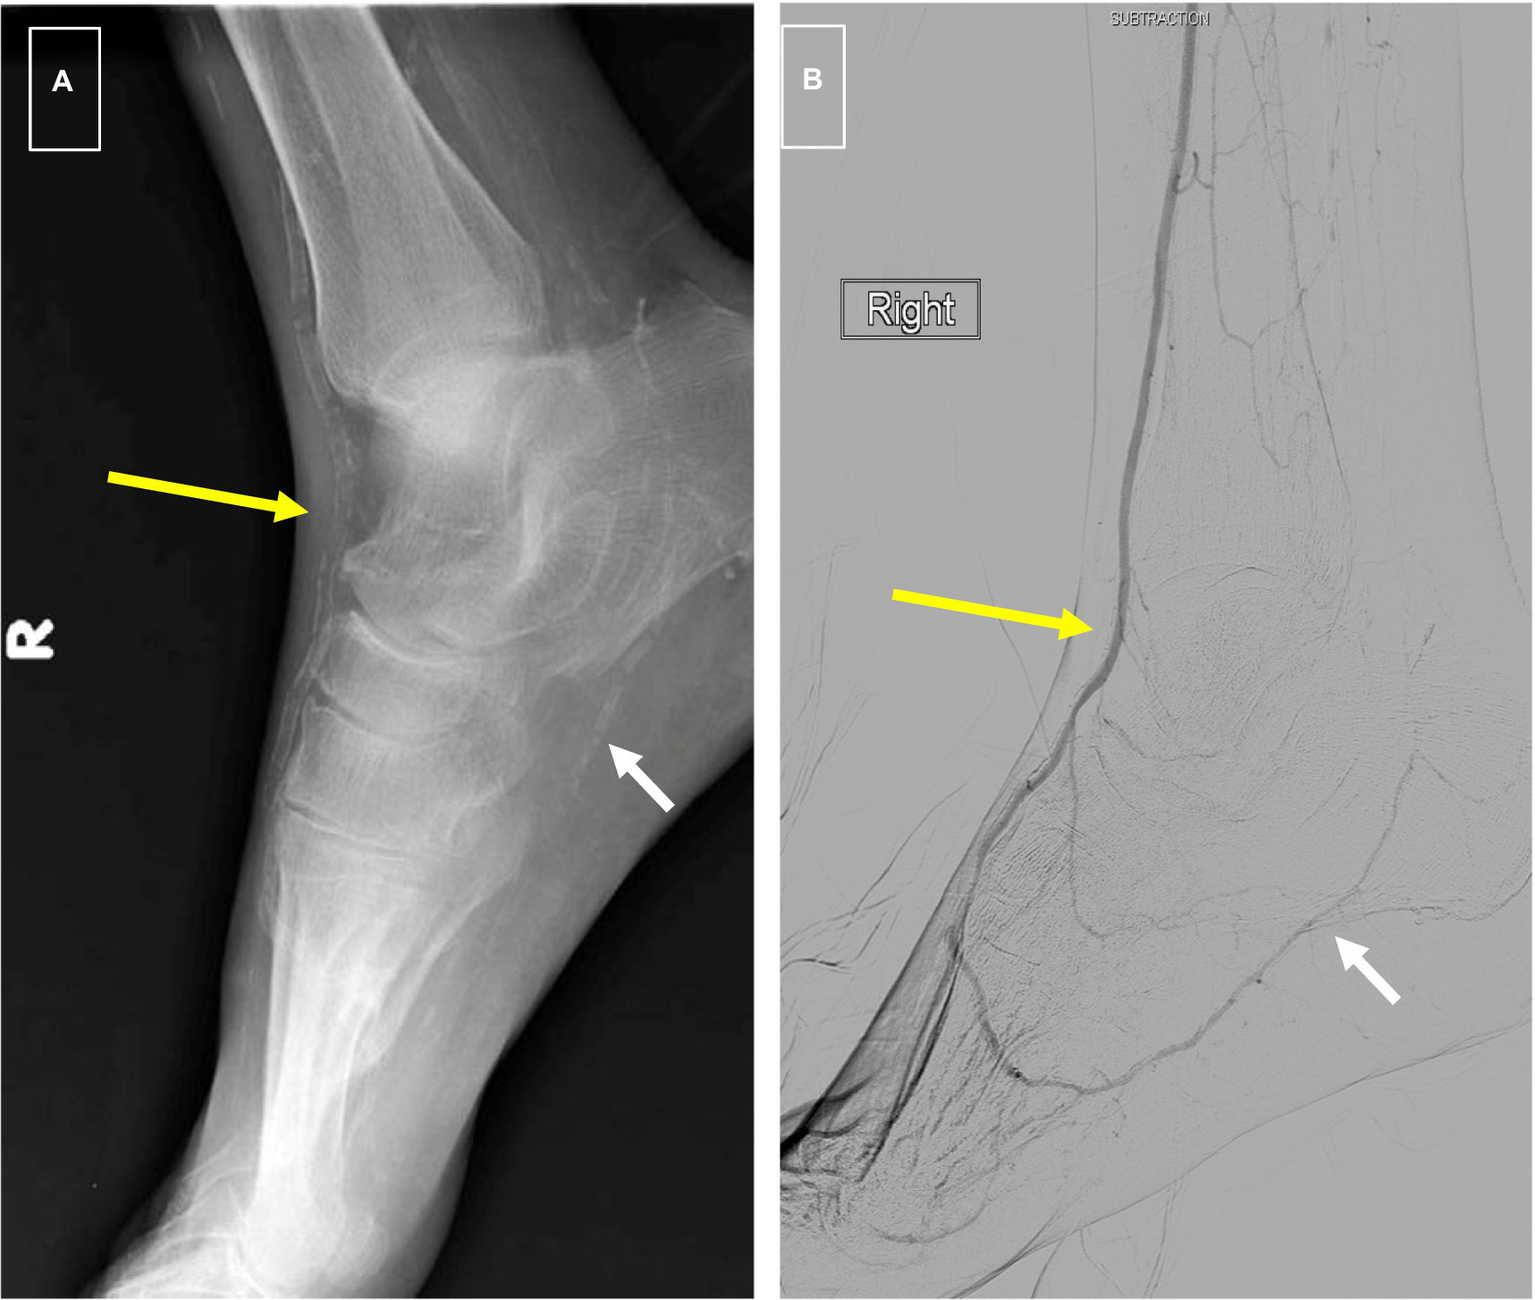

The association of MAC with peripheral atherosclerosis is well known. In 1988, Everhart et al. published their longitudinal findings on 4,553 Pima Indians who were followed over a period of 20 years (40). Patients with diabetes and MAC as defined by a linear appearance of calcifications on x-rays of the hands, feet, calf regions, and thighs had a 5.5-fold increased risk of major amputation, and 1.5-fold mortality rate compared to diabetes patients without it (Figure 2). More recent studies have confirmed a predictive role for MAC on limb outcomes, and several investigators have shown an independent association between it and the severity of PAD as well as the risk of major amputation (5–7). It is noteworthy that traditional tests for PAD such as the ankle-brachial index may be inaccurate in patients with calcified arteries, making it difficult to assess the true severity of ischemia using standard measures. In a study involving 116 patients with symptomatic PAD, we showed that increasing calcification scores correlated with the extent of ischemia, and that this relationship was maintained after adjustment for cardiovascular risk factors and the extent of occlusive disease (6).

Figure 2

(A) Foot x-rays showing typical “railroad track” appearance of dorsalis pedis artery signifying medial calcification (long yellow arrow) and “patchy” appearance of intimal calcification in plantar artery (short white arrow). (B) Digital subtraction arteriogram from same patient showing a patent DP (long yellow arrow) as is typical of medial calcification and high-grade stenosis of plantar arteries associated with intimal calcification (short white arrow).